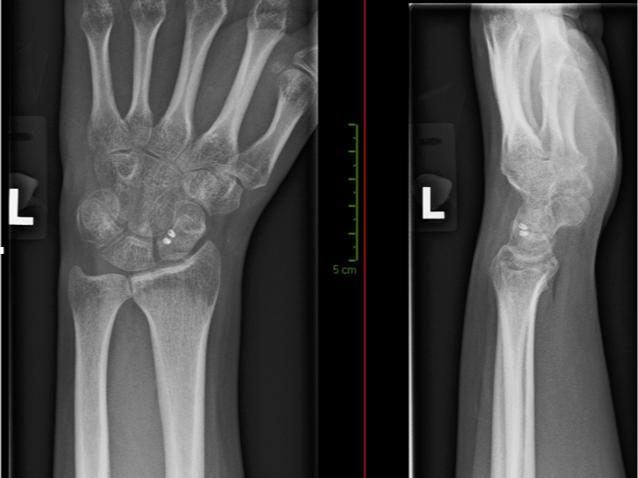

The usual recommendation in a young person with good bone and no complicating factors is to repair the ligament surgically. This operation involves opening the wrist joint to get the scaphoid and lunate bones back into their normal position, then fix them in position with metal pins, before repairing the ligament back onto the bone using a special bone anchor screw.

The metal pins are kept in for around 12 weeks after the surgery, and the wrist is in a plaster cast for all of this time. Ligaments take a long time to heal, so we always try to stay on the safe side with the length the wires are in for. They are usually removed in the theatre with local anaesthetic, because the cut ends are well under the skin.